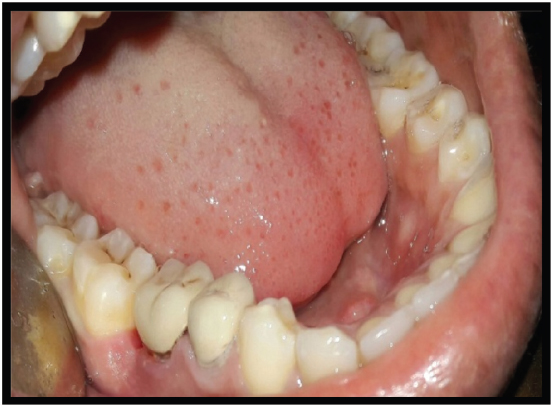

A 26-year-old female patient presented to the Faculty of Dental Sciences at King George’s Medical University, Lucknow, with the primary complaint of pain and sensitivity in the right lower posterior region persisting for the past 3 months. The pain was triggered by mastication and was relieved thereafter. A radiograph (IOPA) revealed periodontal bone loss affecting the coronal third of the distal root compared to the mesial root, and it showed periapical radiolucency at the distal root [Figure 7]. The periodontal support of the mesial root of tooth 46 was deemed adequate. Based on these findings, the diagnosis of chronic irreversible pulpitis associated with the lower right mandibular molar, along with furcation involvement, was established [Figure 8]. It was determined that the distal root should undergo hemisection subsequent to the completion of endodontic therapy for the tooth, in accordance with the methodology employed in Case 1 [Figures 9]. The hemisection of the distal root was executed using a vertical cut technique to effectuate separation. The crown was sectioned using a tapered fissure carbide bur until it reached the furcation. The procedure was thoroughly elucidated to the patient, and informed consent was duly obtained. Following the administration of local anesthesia, a mucoperiosteal flap was reflected to expose the area designated for hemisection. The hemisection procedure was performed on tooth 46 [Figure 10], after which the flapwas repositioned and sutured using 3-0 silk nonresorbable interrupted sutures. Definitive restorative therapy was conducted 6 weeks after the hemisection, which involved the placement of a three-unit porcelain fused-to-metal fixed partial denture to replace the distal root of the mandibular first molar, second premolar, and second molar [Figure 11]. At the 1-year follow-up appointment, the patient reported being asymptomatic.

Figure 8. IOPAR showing involved furcation

thumb